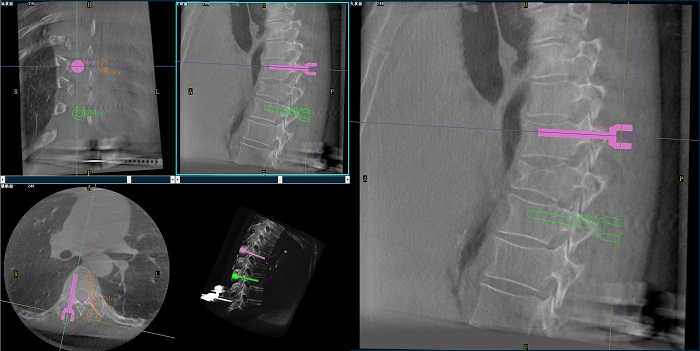

②机器人辅助胸椎手术操作难点之路径规划

人体胸椎的椎弓根较腰椎更狭窄,周围有重要的神经和血管,选择合适尺寸和长度的螺钉至关重要。螺钉过粗可能损伤椎弓根,过细容易发生形变,固定强度不够;螺钉过长可能穿透椎体前缘,造成损伤,过短则固定不牢。

使用机器人辅助手术,医生不仅可以在影像的引导下,一次性完成多枚螺钉的路径规划,提高手术效率,而且可以精确地选择螺钉的角度、直径和长度,提高手术的成功率。